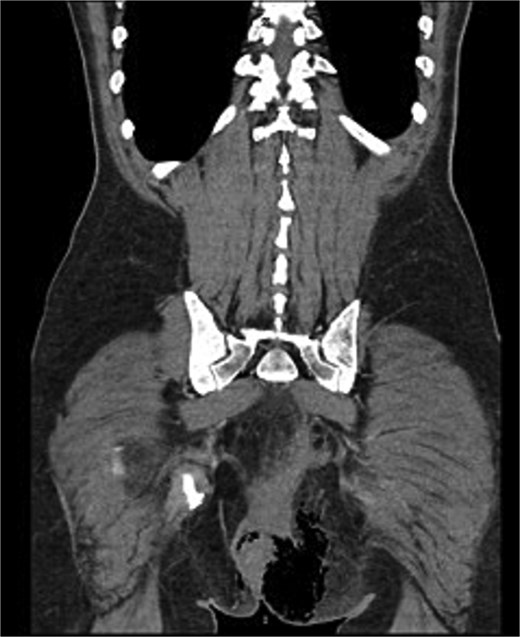

Urgent surgery was performed, including debridement of necrotic tissue, biopsy of the distal rectal lesion, and diverting colostomy. The patient’s postoperative course was favorable (Fig. 3).